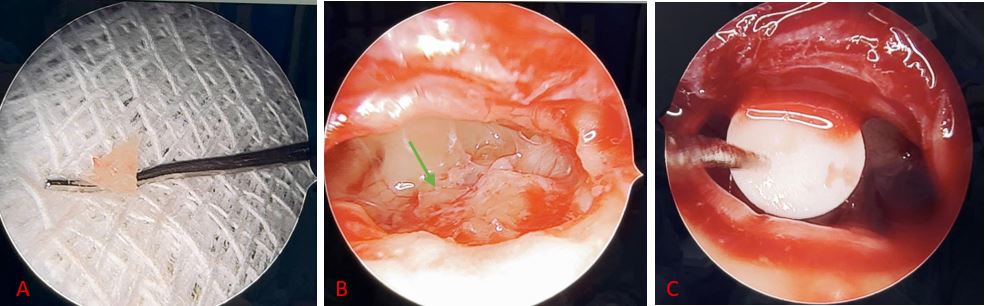

Với chẩn đoán Dị tật bẩm sinh đơn độc chuỗi xương con (ICOCM) tai trái loại II theo Cremers và Teunissen , bệnh nhân được chỉ định phẫu thuật tai trái với phương pháp thay thế xương con toàn bộ (TORP). Trong quá trình phẫu thuật ê – kíp đánh giá chuỗi xương con ghi nhận dị dạng và mất cành xuống xương đe, dị dạng xương bàn đạp (Hình 3A). Sau đó ê – kíp phẫu thuật tiến hành lấy bỏ xương đe, xương bàn đạp dị dạng (Hình 3B). Tiếp theo, tiến hành lấy sụn bình tai đặt bảo vệ cửa sổ bầu dục, đặt trụ dẫn, đặt sụn bình tai giữa trụ dẫn và màng nhĩ theo chiều dọc (Hình 3C).

Hình 3. A. Xương bàn đạp dị dạng; B. Lấy bỏ xương bàn đạp dị dạng (mũi tên màu xanh). C. Đặt TORP